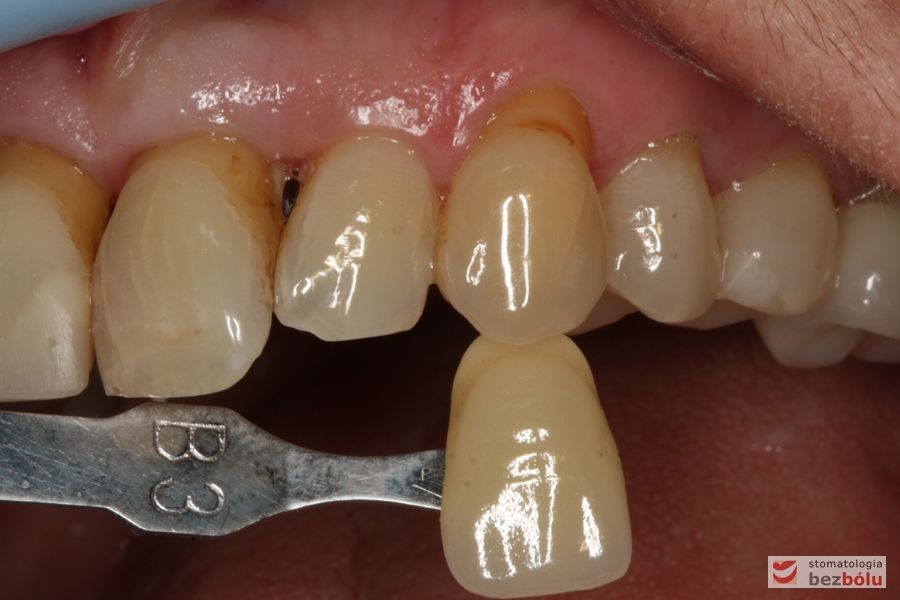

Dobór koloru ostatecznej odbudowy protetycznej - dopasowanie odcienia do barwy kła i antagonistów

Dobór koloru ostatecznej odbudowy protetycznej – dopasowanie odcienia do barwy kła i antagonistów